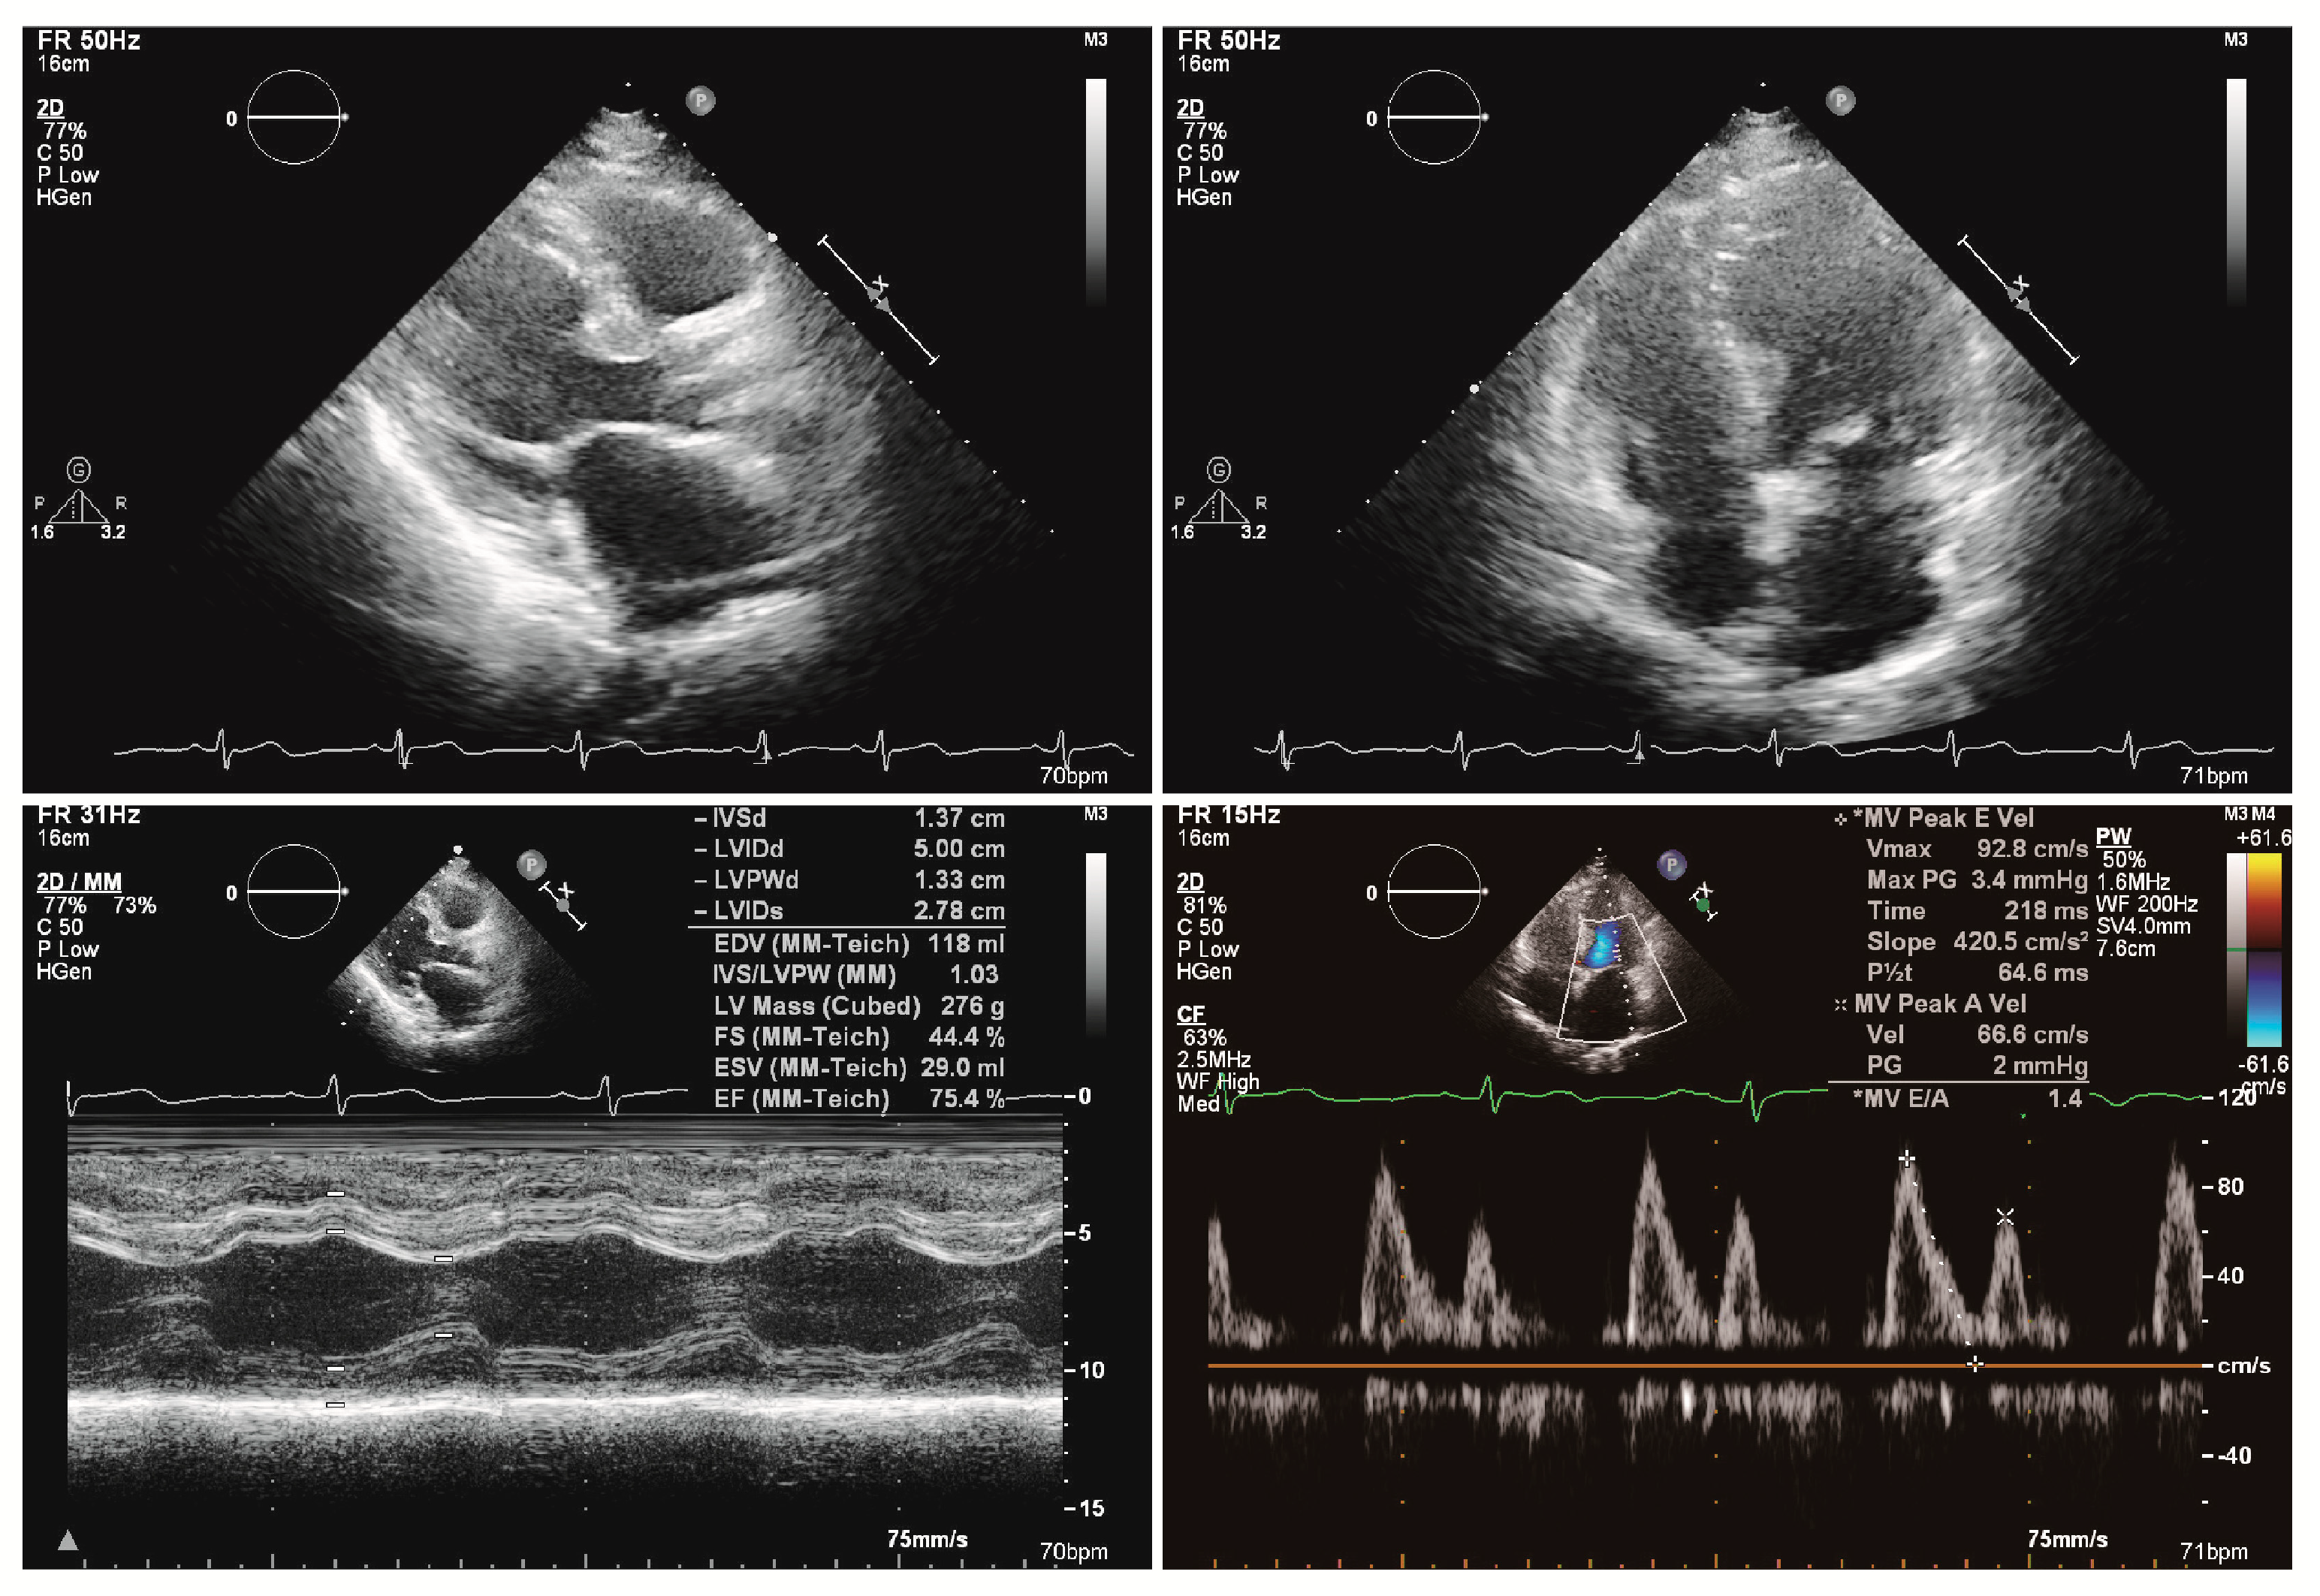

2. Case Presentation